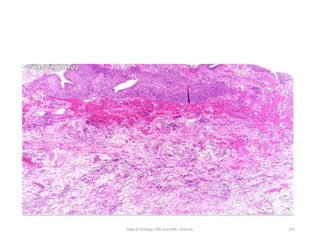

• Muscle invasive

• Histology:

• Invading urothelium shows irregular nests, single cell

infiltration or tentacular finger-like projections

• Stromal response

-desmoplasia,

-retraction or

-inflammation.

• Assess level of invasion for staging

.

• Presence and status of involvement of muscularis propria

should be reported in TURBT specimen for adequate staging.